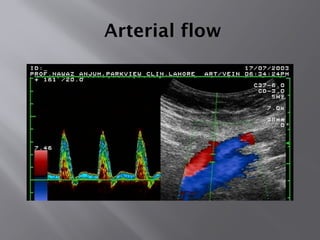

Arterial flow

Venous Flow